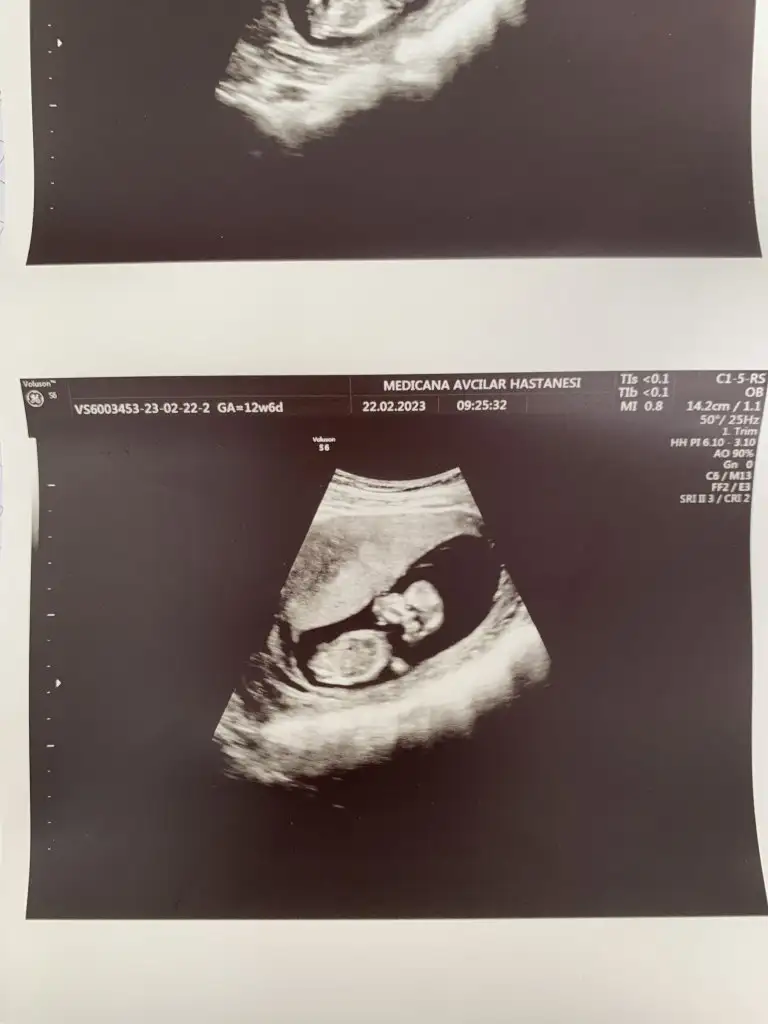

Merhaba arkadaşlar bu benim ilk hamileliğim o yüzden çok bilgim yok, bugün 12+4 de ikili ultrason yapıldı doktor cinsiyeti ne hissediyorsun dedi açıkçası içime herhangi bir şey doğmuyor yani kız yada erkek diye. Doktorum benim içime kız doğuyor haberin olsun dedi. Çok sevindim ama sonrasında kime söylesem hemen moda girme o sadece bi tahmin daha belli olmaz diyorlar. Erkek bebek kendini erken gösterir kızı 16. Haftaya kadar zor görüyorlar nasıl hemen söylemiş falan dedi yani şimdi kız dedi ama sonradan yanılma gibi bir payı var mı ? Çok mu erken cinsiyet için. Üstelik doktor çok sevindiğimi görünce yine de herkese söyleyip pembe şeyler alma hemen netleşsin , bana da bu zamanlar kız demişlerdi şimdi oğlum var dedi , ama 3 kez de üstüne basarak kız gibi görüyorum dedi. Açıkçası herkesin yorum yapması biraz böyle kafamı karıştırdı. Kız yada erkek asla farketmez sonuçta kızımda yok oğlumda ama insan ilk gebelik heyecanıyla bilip herkese söylemek istiyor sanırımböyle öğrenip sonradan cinsiyet değişen doktoru yanılan var mı ? Eskiler de çokmuş bu durum ama şimdi cihazlar çok gelişmiş olma diye umuyorum. Bu Arada fotoğrafta yüklüyorum belki sizde bi tahminde bulunursunuz

Nubu tam net gorunmuyo kapatmis ama kafa yapisi kiza benziyo yuvarlak kiz olma ihtimali yuksekBu foto 11haftalik cnm

Nubu tam net gorunmuyo kapatmis ama kafa yapisi kiza benziyo yuvarlak kiz olma ihtimali yuksek

Doktor kiz oldugunu soylemis olmali bacak arasi bos cnku

Beklemekte fayda var bazi bebekler gostermiyo usg fotolari yaniltabiliyo cekme acisindangorunmiyor kucuk dedi